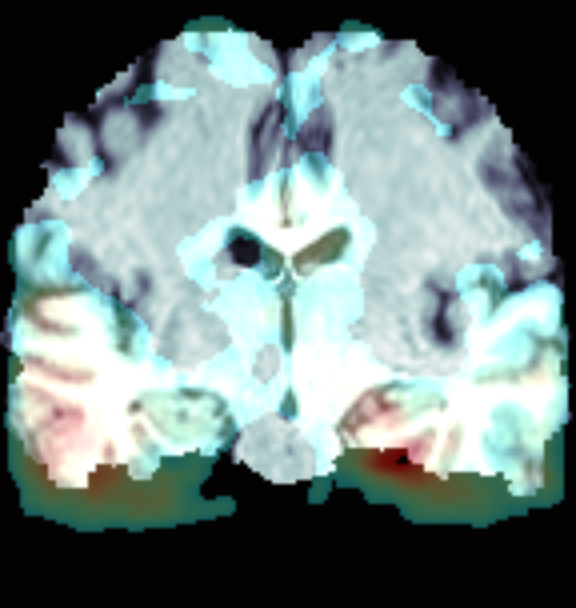

3. 热力图与原始图融合优化

上面图像融合之后存在的问题是,前景热力图完全遮挡了原图,使得最终的展示图中,原图结构存在模糊。首先对热力图进行优化,使背景颜色变为白色且去掉一些权重过小热力。然后将热力图剩余的部分叠加到原图上。

使用上面的函数(上面的图像不正,首先向左旋转90°,之后再进行融合):

heatmap = np.load("CNcam.npy")

img_data = np.load(img_path)

heatmap = np.where(heatmap < 0.3, 0, heatmap) * 255

img_data = np.rot90(img_data[:, 84, :], 1) # 向左旋转90度

heatmap = np.rot90(heatmap[:, 84, :], 1)

img_fusion(heatmap, img_data, r'tmp.png')

绘制结果: